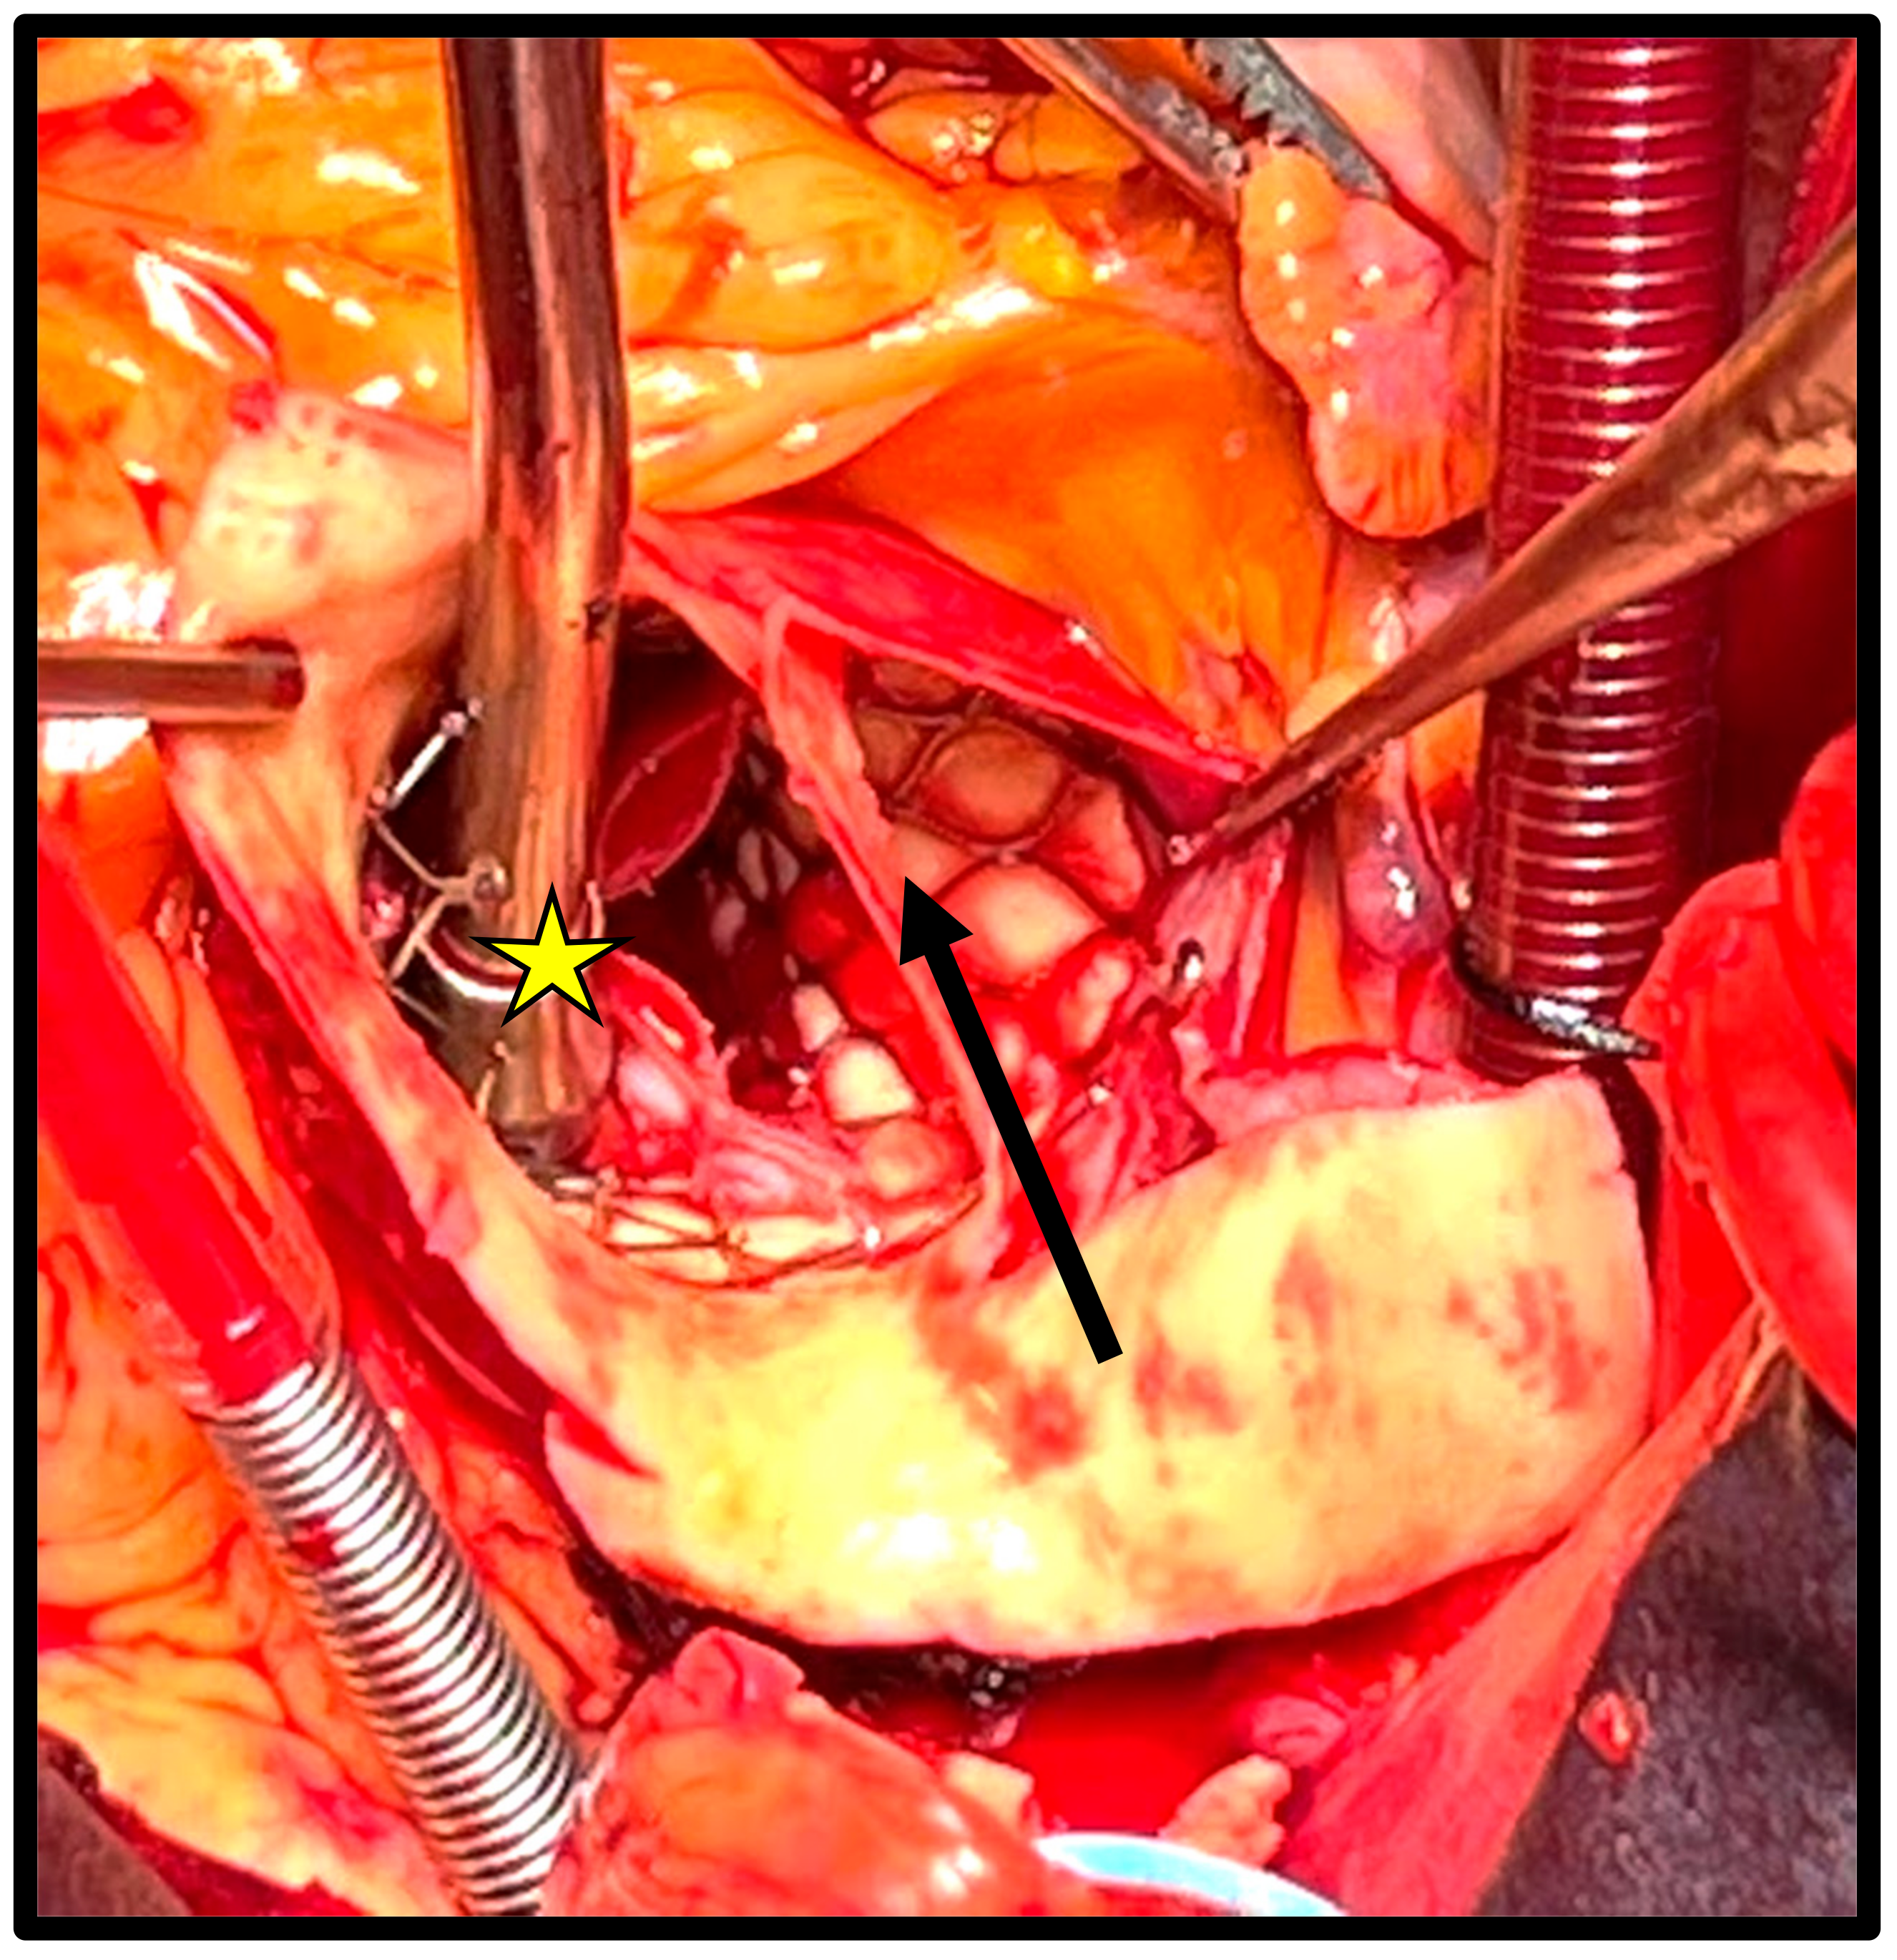

The majority of patients underwent TAVR with a self-expanding prosthesis (16 [76%]), and the rate of complications when comparing the two types of devices was not statistically significant (p = 0.09). A total of 11 patients (52%) presented acute complications, of which the most common were aortic dissection (n = 4 [19%], Figure 1) and left ventricular perforation (n = 3 [14%]). The most common chronic complication was early endocarditis (n = 5 [24%]), followed by early prosthetic valve dysfunction (n = 3 [14%]); both complications were assessed according to the VARC-3 criteria.

Figure 1. Acute aortic dissection of the aortic root and ascending aorta following implant of a self-expanding TAVR and originating from the outflow stent. The black arrow shows the dissection flap. The yellow star above the suction device shows the correct position of the TAVR.